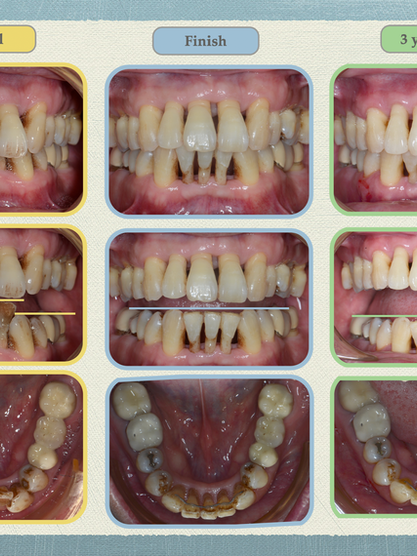

有嚴重牙周病,可以矯正嗎?

牙周病患者在進入矯正治療前,必須先進行過完整的牙周治療與再評估 。評估牙周是否穩定包含一些指標 ,確認牙周狀況穩定後醫師會給予能否進行矯正治療的建議 。在矯正醫師端評估時 ,還是會就患者需求如:是否要同時改善暴牙 、戽斗?能否同時進行重建或是先矯正完再重建?以及當下牙周狀態是否穩定等進行具體資料收集、評估後再給予建議。 在矯正過程中很重要的是 , 仍須維持在牙周醫師的固定3-6個月回診一次(視牙周嚴重程度) , 才能確保在矯正過程中仍然保持良好的牙周健康。